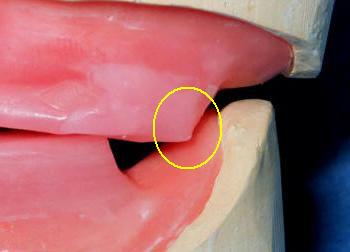

- A veces el rodete superior contacta la

base del rodete inferior, como muestra la figura siguiente.. Debe remover el

contacto acortando la cera del rodete superior.

- O la base del

rodete inferior interfiere en el registro de céntrica tocando la

placa base del rodete superior.